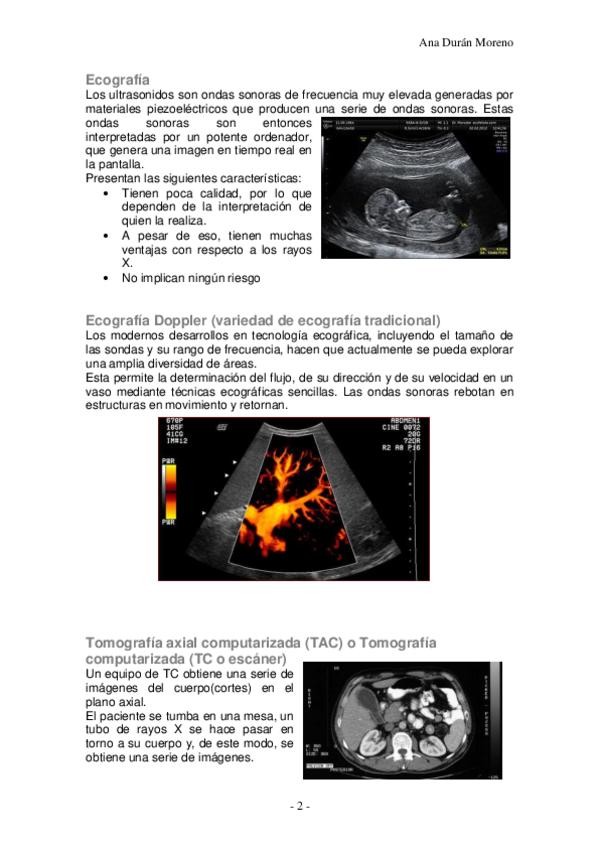

He publicado nuevos apuntes de 1º Anatomía Humana I: 02.Técnicas de imágen.pdf